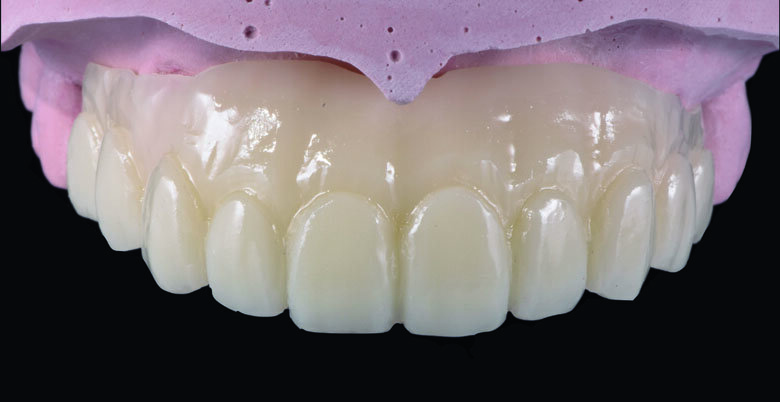

Fig 8. Full-contour waxing was made according to teeth proportion and position.

Fig 11. Milled Full-contour PMMA bridge

Fig 12. cutback was made to create gingival space for pink composite layering.

Aesthetic analysis was performed with evaluation of the smile line, incisal profile, length and proportion. Diagnostic wax-up was fabricated according to the aesthetic evaluation. (Fig. 8)

Provisional full arch bridge fabrication (Fig. 8 - 19)

Preparation cast with a diagnostic wax-up ca st was sent to a local laboratory for scanning and transforming into STL (Stereolithography) digital impression file. (Fig 8,9.) Two sets of STL impressions were super-imposed in the software in order to subtract the overlapping data. This process was done in order to transform the diagnostic wax-up into the STL digital impression. Consequently, the STL data was sent to the laboratory for milling. (Fig10.) A monochromatic milled-PMMA temporary bridge was fabricated in a local laboratory and returned to the dentist for composite layering. (Fig 11.) Gingival cutback was made to create sufficient gingival space for pink composite layering (Fig 12). Prior to composite layering CeraResin Bond 1 was applied and left for 10 seconds to prime the surface, followed by application of CeraResin Bond 2 for 10 seconds and light cured for 20 seconds (Fig 13.). Ceramage Indirect Composite gingival shade GUM-O (GUM Opaque) was applied to mask the color of PMMA (Fig 14.). GUM-D (GUM Dark) was applied on the attached gingiva area to the buccal flange (Fig 15.). GUM-L (GUM Light) was applied in the region of free gingiva (Fig 16.). F-GUM-R (Flowable GUM Red) and F-W (Flowable GUM White) were painted to mimic the mucogingival junction and vascular alveolar mucosa (Fig 17.) GUM-T (GUM Translucent) was applied to reproduce of reddish translucent gingiva areas (Fig 18) to achieve natural gingival aesthetics.

Contouring, Finishing and Polishing of temporary restoration

Meticulous finishing and polishing of the restoration is a crucial step to achieving the desired aesthetics. Dura-Green stone was used to contour the macro anatomical details while the Robot Carbide Fissure Bur was used to shape the interproximal and papilla areas. The course silicone points followed by Dura-Polishing paste Al2O3 with a medium strong brush was used to finish and pre-polish the restoration. Dura-Polish DIA, diamond polishing paste was applied with a fine brush followed by the cotton buff to achieve the final high-luster polishing (Fig 19.)1.